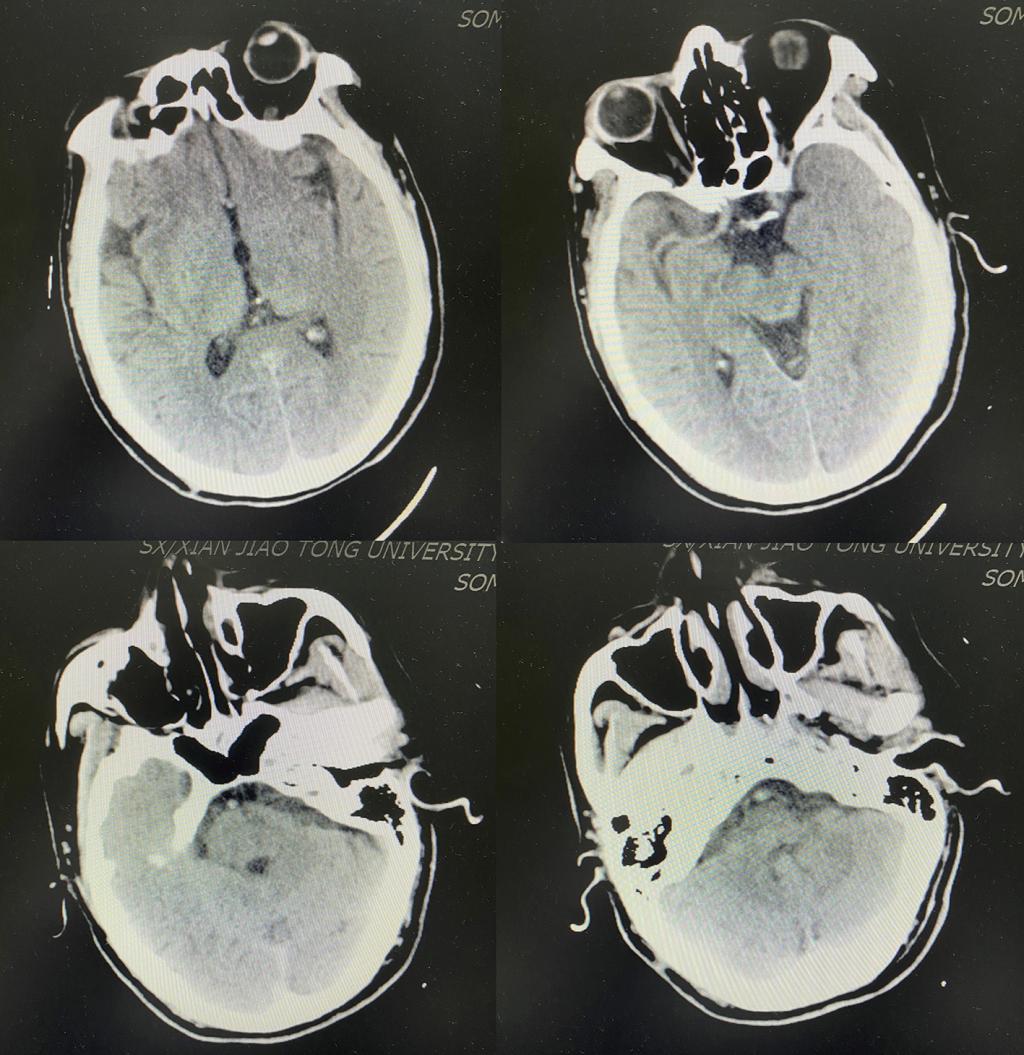

颅脑CT未见出血

术后复查颅脑CT无脑出血转化